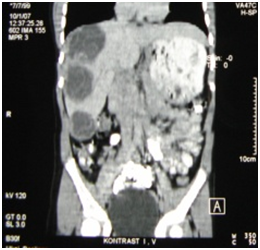

Figure 5 Total pericystectomy for gyant cyst of the right liver lobe in close relationship with the caval vein and the right portal branch. This patient underwent PAIR 1 year before surgery.

Sixteen cysts were excised in 10 patients. Nine patients underwent radical surgery; 5 had multiple cysts and were submitted to hepatic resection (1 right and 2 left hepatectomy) or multiple total pericystectomy with closed cyst. Four patients with single cyst underwent total pericystectomy with closed cyst. Only 1 patient underwent a non-radical operation and a subtotal pericystectomy was performed. In this case the cyst was opened and a small piece of the pericystium was left in place close to the right branch of the portal vein and the bile duct. A cysto-biliary fistula with the right posterior bile duct was sutured after washing of the biliary tree. Only in one case intermittent Pringle maneuver was used to control bleeding. In the other cases the inflow was controlled by selective clamping, if necessary. In 2 cases previous clamping at the origin of the right hepatic vein was performed before dissection of the vein from the pericystium. Intraoperative ultrasound was necessary only in one case of subtotal pericystectomy. It was always possible to dissect the main veins from the pericystic wall (Figure 2-4), while it was necessary to sacrifice the structures of the portal triad when they were fused in the pericyst. Mean operative time was 236 min. All patients were extubated at the end of the procedure. Mean postoperative stay was 5.2± 2,52 days (range 3-10), with no mortality and only 1 low output biliary fistula in the case of subtotal pericystectomy that healed after 9 days. Postoperative stay was longer for children because they lived far from the hospital. Mean follow up is higher than 3 years and until now no recurrence were observed (Figure 5).

Figure 4 After adequate exposure, it’s always possible to dissect the cyst from main hepatic veins. In this case a cyst of segment IV-VIII is dissected from middle hepatic vein